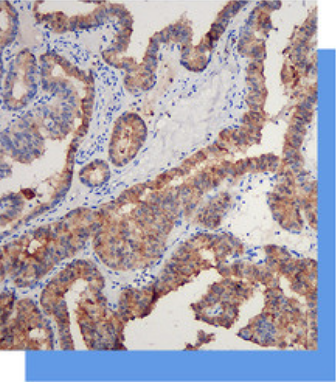

Galectin-3抗体试剂

Galectin-3是一个同型细胞粘附凝集素,它

是由β-半乳糖苷键结合蛋白和一个层粘连蛋

白构成的嵌合体结构。细胞表面的Galec-

tin-3主要作用和同类细胞间的粘附有关,它可以

下调某些盲肠癌和乳腺癌相关蛋白的表达,促进

这些肿瘤的转移。研究资料可以Cytokeratin19

联合使用于甲状腺乳头状腺癌的诊断,是间变性

大细胞淋巴瘤很有效的标记,还可以作为肿瘤恶

化程度的一一个参考指标。